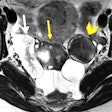

MRI aids patient selection in fertility preservation therapy